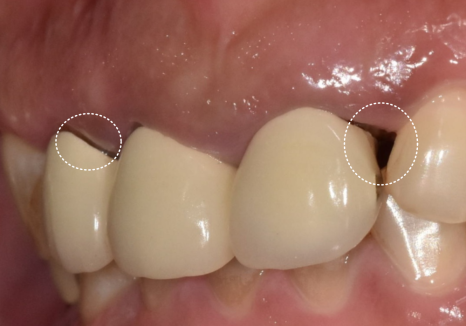

오른쪽 위 어금니에 씌운

10년 된 보철물이 갑자기

툭 빠져서 내원하시게 되었는데요~

겉보기엔 멀쩡해 보였지만

보철물이 빠진 자리의

내부 치아 2개는 이미 까맣게

썩어있는 상태였습니다.